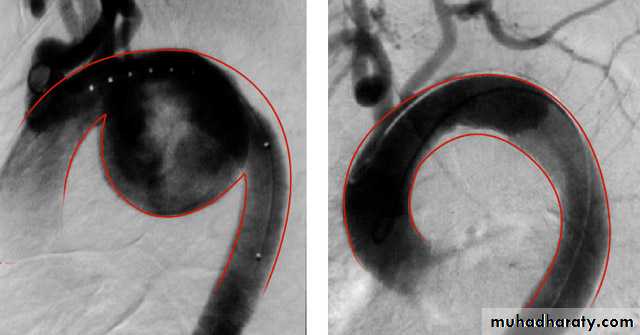

• Angiography

Angiography: